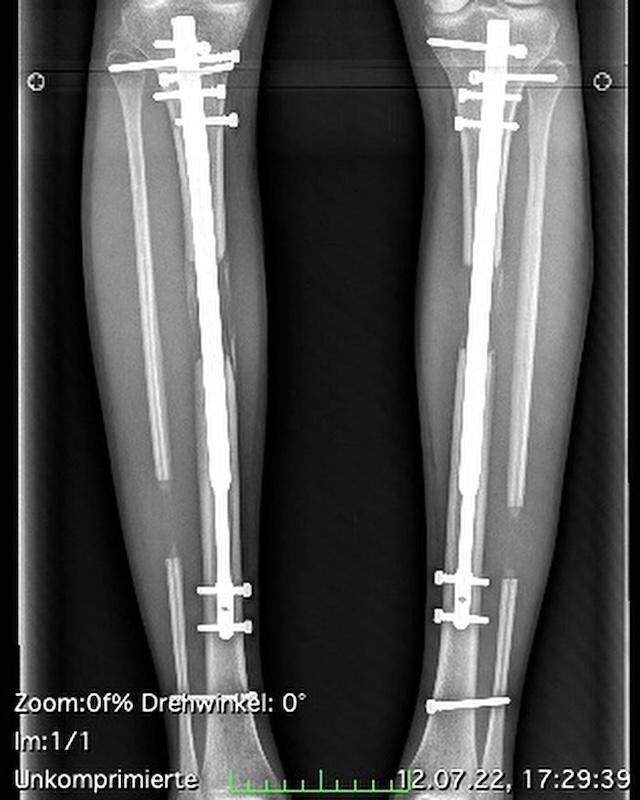

Theresia’s leg-lengthening journey involved multiple surgeries that spanned several years. The process began with an osteotomy, where surgeons cut her thigh and shin bones into two segments. Metal rods were then inserted to gradually separate the bone segments, allowing new bone tissue to form in the gap. Surgeons used two types of devices for this procedure:

- External Fixators: These light metal frames, attached to the bones with pins and wires, protrude several inches from the body. Patients or caregivers manually adjust the screws to achieve the desired length.

- Internal Rods: This newer method involves implanting a screw-like device inside the bone, which can be adjusted using a remote control to trigger magnetic or mechanical elongation.

Theresia underwent multiple rounds of surgery, enduring immense pain and discomfort as her legs were stretched by approximately one millimeter per day.